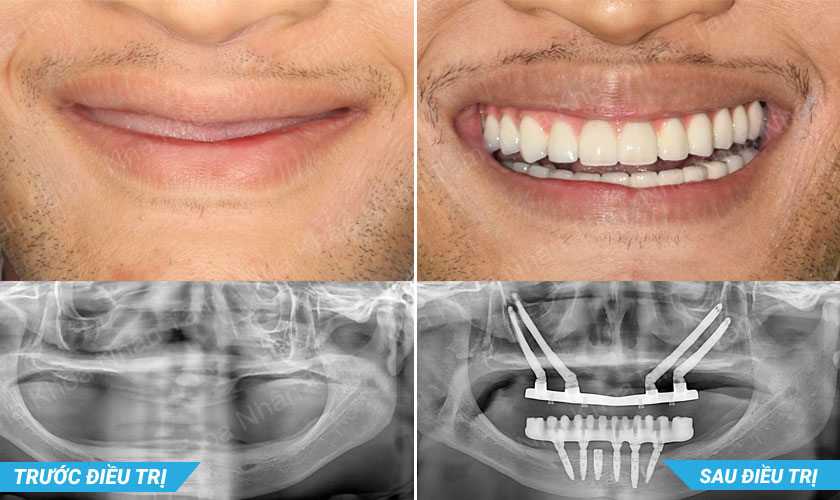

4/8/2023: Báo cáo viên tại Hội nghị MIDEC 2023 tại Malaysia

Tại Hội nghị MIDEC 2023 diễn ra tại Malaysia, Tiến sĩ, Bác sĩ Võ Văn Nhân đã trình bày báo cáo với chủ đề “Giải pháp đương đại trong phục hồi implant toàn hàm: chỉ định, vật liệu và công nghệ”. Bài báo cáo cùng các ca lâm sàng thực tiễn đã thu hút sự quan tâm và đón nhận tích cực từ các bác sĩ, chuyên gia quốc tế.

Thông qua chia sẻ, bác sĩ Nhân nhấn mạnh hiệu quả của việc ứng dụng công nghệ hiện đại trong phục hình implant – giúp đơn giản hóa quy trình điều trị, nâng cao độ chính xác và mang lại sự an toàn tối ưu cho khách hàng.